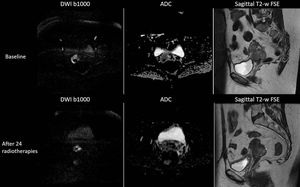

DWI shows that there is an increase in tumour's diffusivity (the ADC value before radiotherapy was 603 μm2/sec, and the ADC value after radiotherapy is 917 μm2/sec) and a decrease in tumour's volume after the radiotherapy. These changes in tumour's microarchitecture are not initially seen using conventional anatomical imaging.